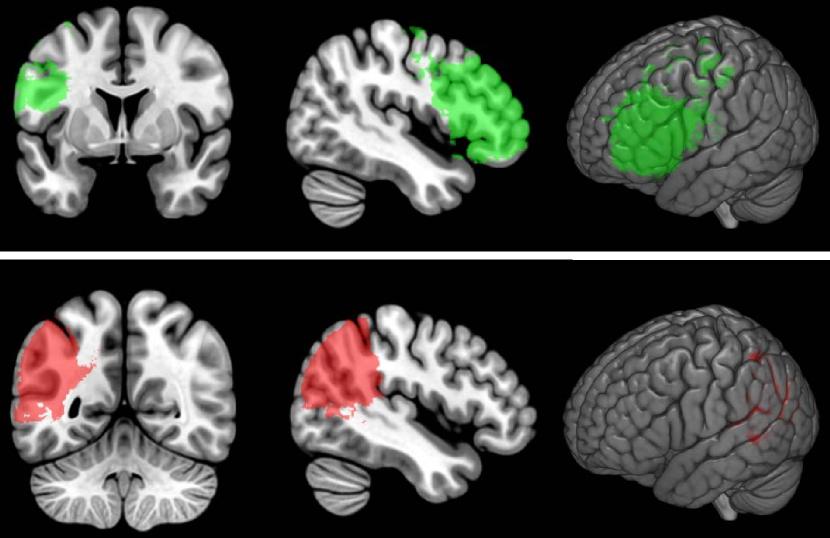

Figure 4 shows the results of permutation-based cluster size correction (at p<0.0001𝑝0.0001p<0.0001) for simulated deficit scores of percent damage in BA 45 (top row) and BA 39 (bottom row). It is immediately apparent that the identified region expends beyond the bounds of the true region, covering an area that is perhaps twice the size of the Brodmann Area where percent damage was used as the behavioral score.

Refer to caption

Figure 4: Results of VLSM analysis of percent damage to BA 45 (top row) and BA 39 (bottom row). Thresholded at voxel-wise p<0.0001𝑝0.0001p<0.0001 and permutation-based cluster size corrected.